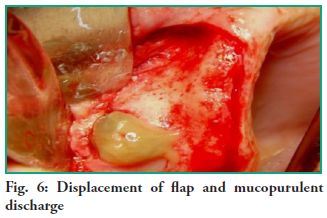

Surgical procedure After administering local anesthesia, a crestal incision was made from the tuberosity area up to around the midline, and a relieving incision near that area. An exploratory puncture, through which a purulent mucus-like content was obtained, was performed before the incision. A full-thickness flap was lifted from the front to the back, exposing a bone fenestration through which an abundant mucopurulent discharge is drained (Fig. 6).

Surgical procedure After administering local anesthesia, a crestal incision was made from the tuberosity area up to around the midline, and a relieving incision near that area. An exploratory puncture, through which a purulent mucus-like content was obtained, was performed before the incision. A full-thickness flap was lifted from the front to the back, exposing a bone fenestration through which an abundant mucopurulent discharge is drained (Fig. 6).